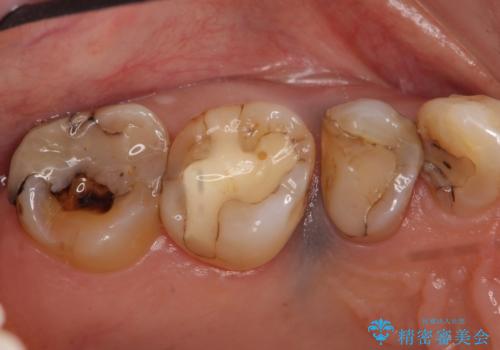

- 右上の奥歯がしみるので診て欲しいといらっしゃった方の症例です。

診査の結果痛みの原因は右上7番目だったため、古い樹脂と虫歯を除去後、オールセラミッククラウンによる補綴を行いました。

また右上5、6番目の歯も治療を希望されたため、オールセラミッククラウンによる補綴を行いました。